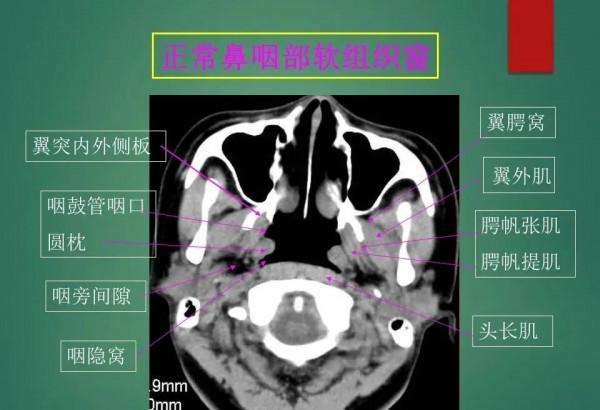

高畫質鼻咽部CT解剖